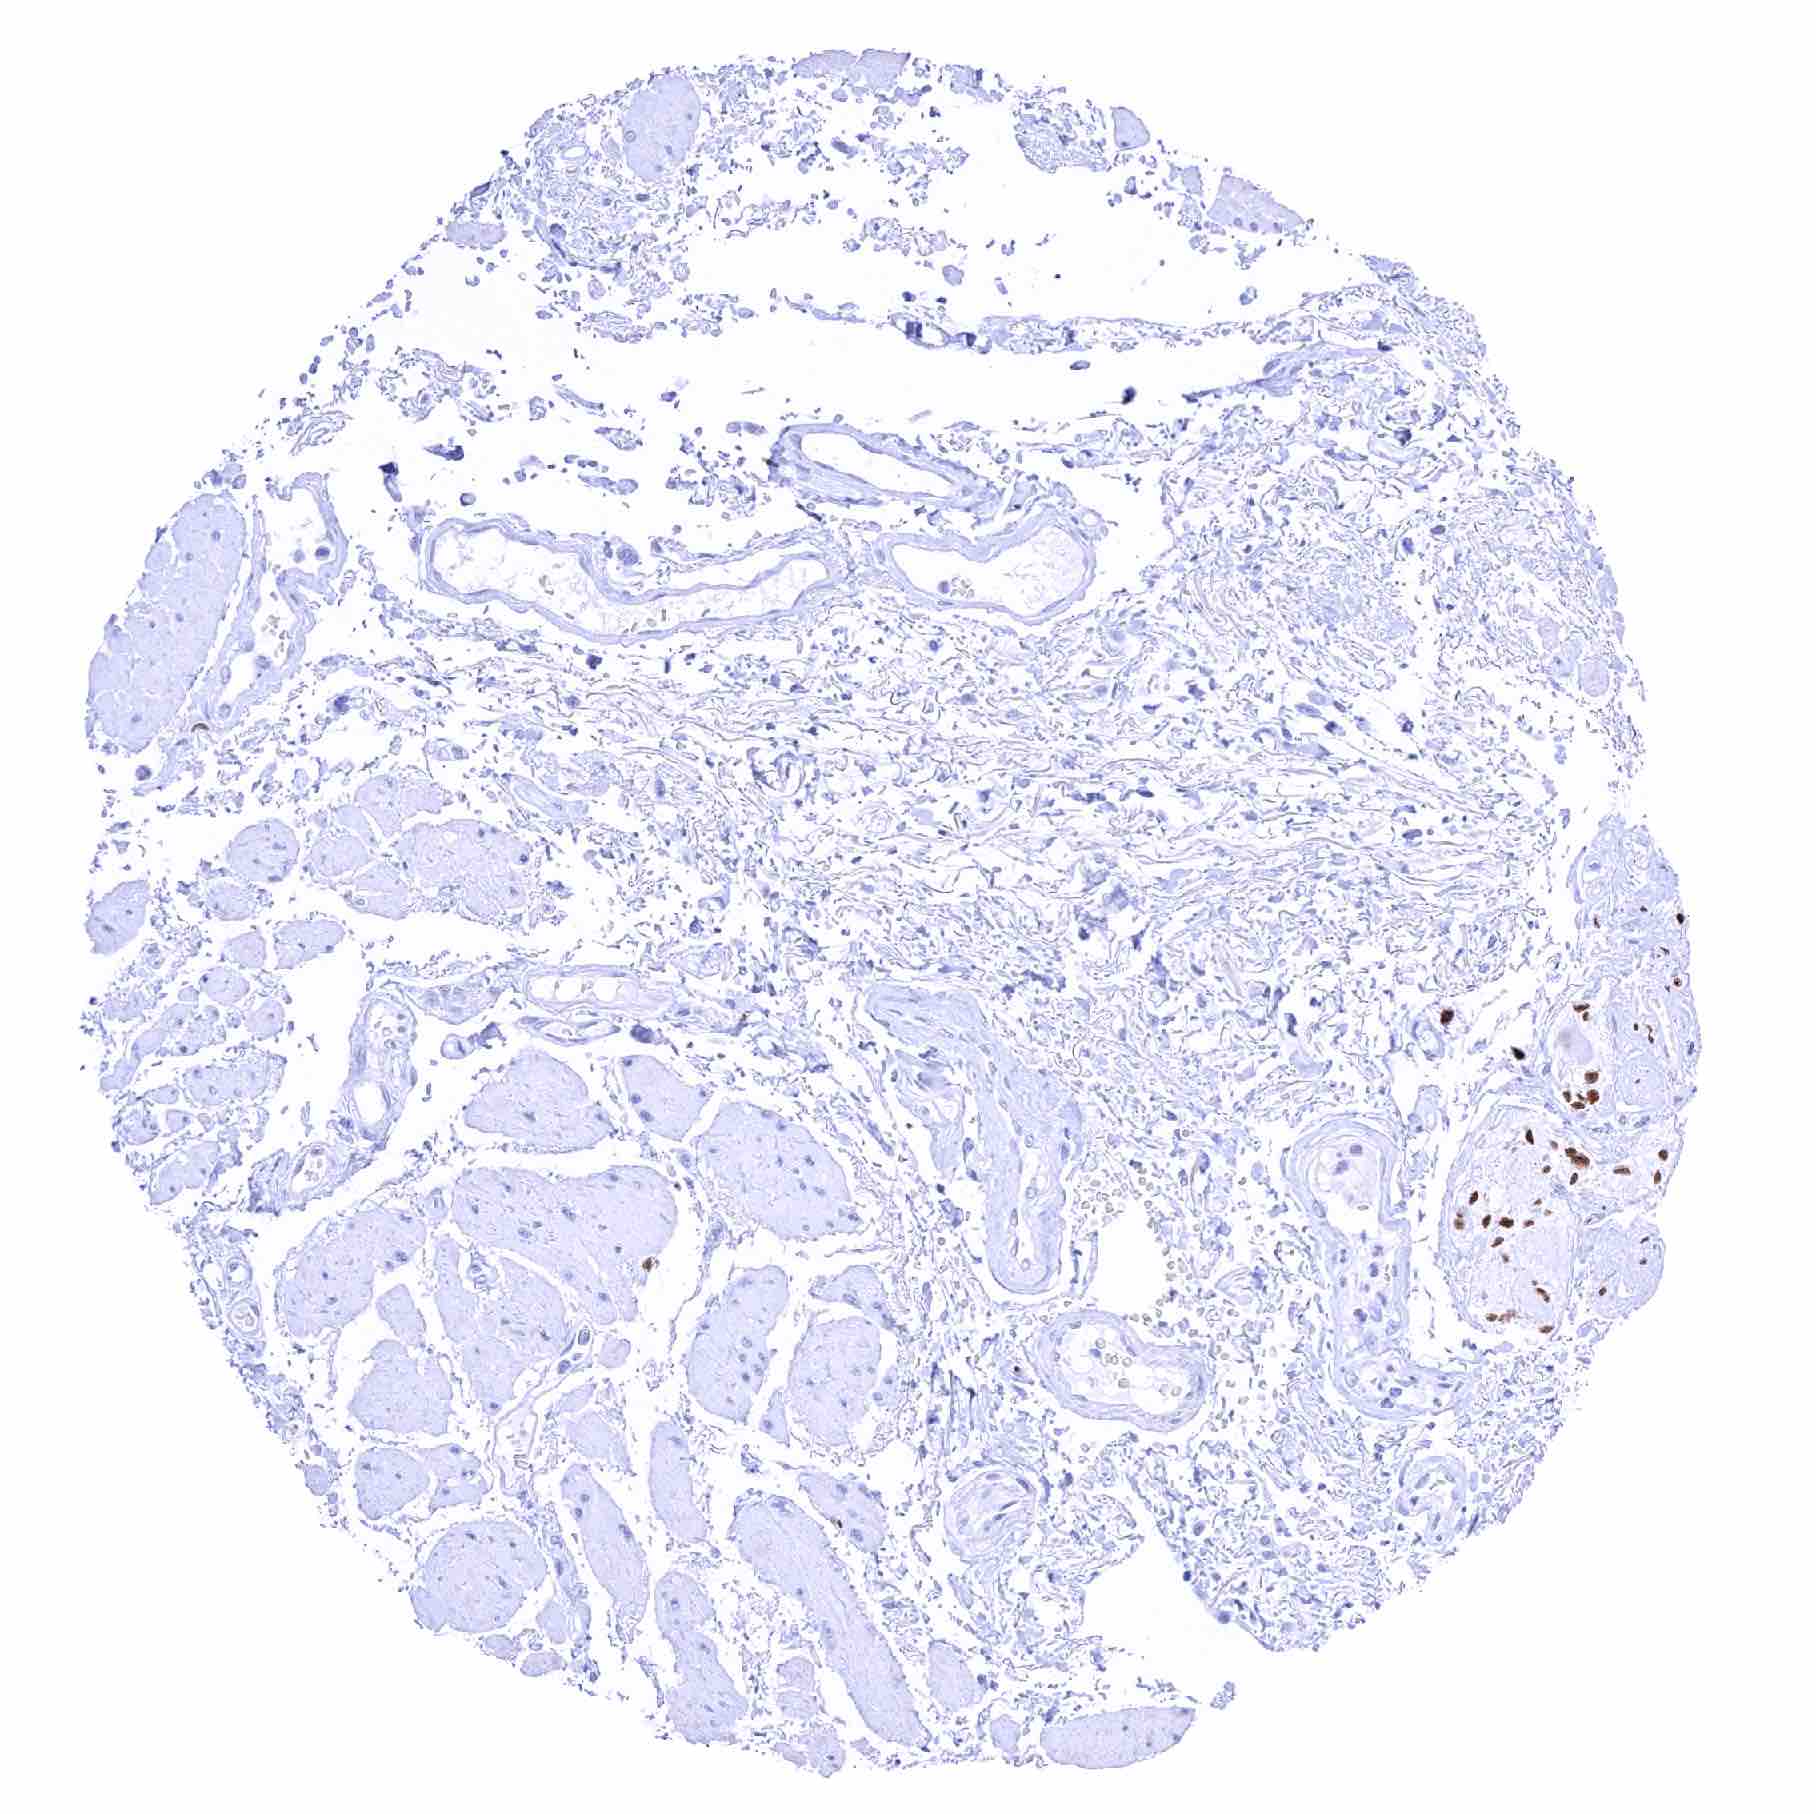

Placenta, early